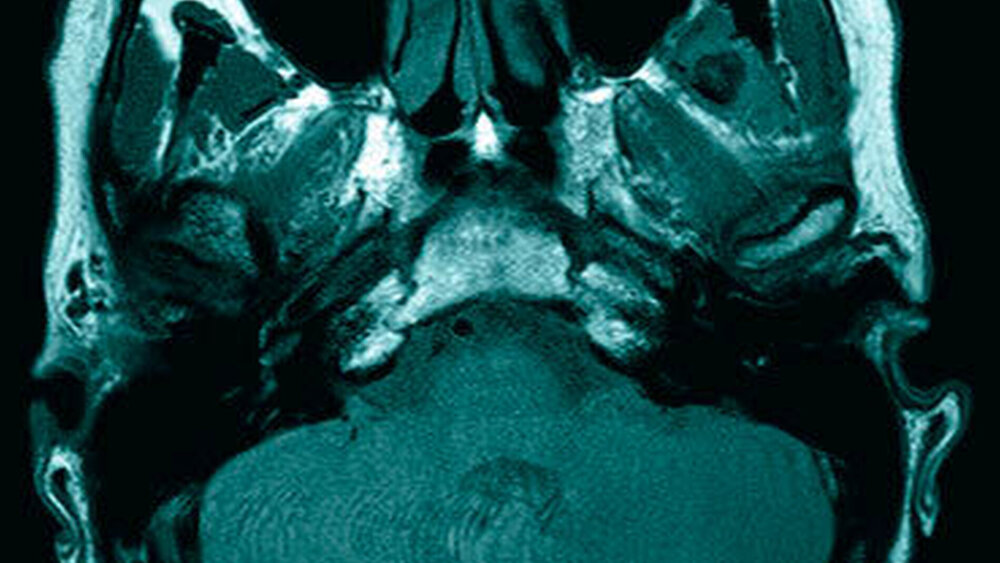

Das neun Tage später durchgeführte MRT zeigte keinen Anhalt für eine Läsion des Diskuskomplexes beidseits. Es wurde jedoch eine umschriebene, teils T2-hyperintense sowie kräftig randständig kontrastmittelaufnehmende Läsion im M. pterygoideus medialis links (axial bis zirka 1,0 cm) angrenzend an den Processus muscularis vereinbar mit einem kleinen intramuskulären Abszess beschrieben (Abbildungen 2 a und b). Des Weiteren erschien der M. pterygoideus medialis links in seinem ganzen Verlauf ödematös verändert, jedoch ohne Anhalt für eine Beteiligung der umliegenden Strukturen wie dem M. pterygoideus lateralis.